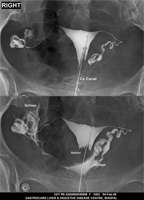

Section: HSG

Total: 49 Cases